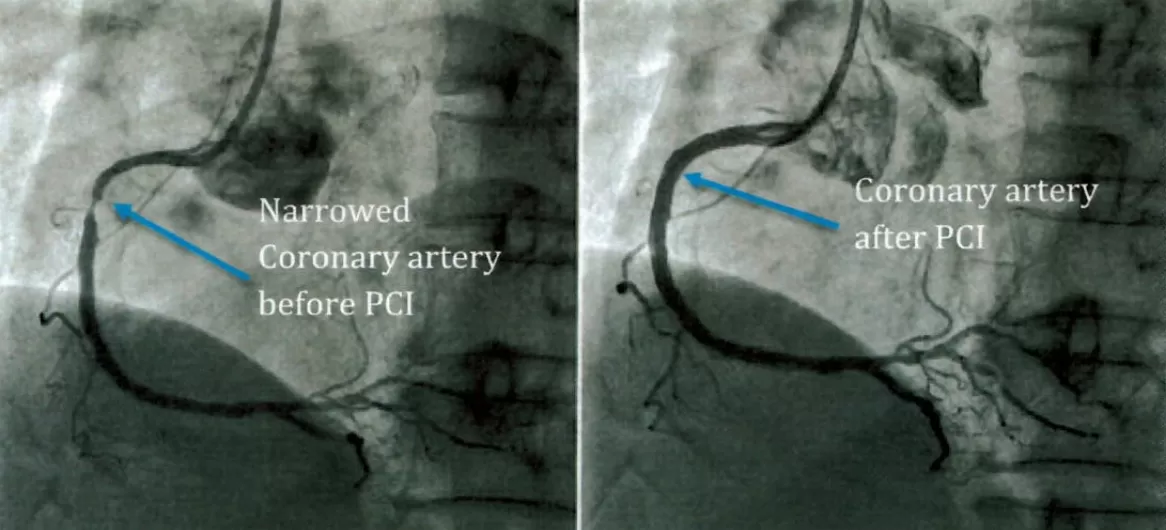

A narrowing or blockage in a coronary artery can cause symptoms such as chest pain or heaviness.

A balloon angioplasty is normally performed (steps 1 &2) before a stent is inserted (steps 3, 4 & 5). A stent is a metal mesh tube that holds back the plaque that has caused your artery to narrow or block.